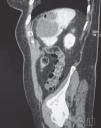

Infecciones por estafilococos